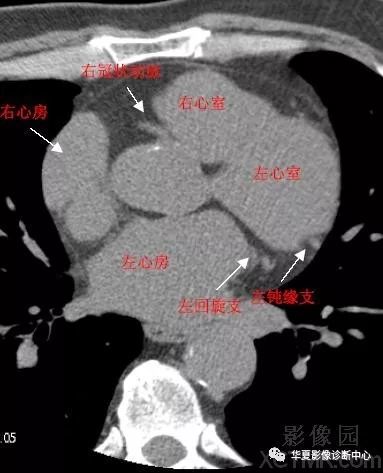

影像解剖|心脏冠状动脉ct解剖中文详细标注(图文)

影像解剖 心脏冠状动脉ct解剖中文详细标注(图文)

带你全面了解心脏冠状动脉ct解剖